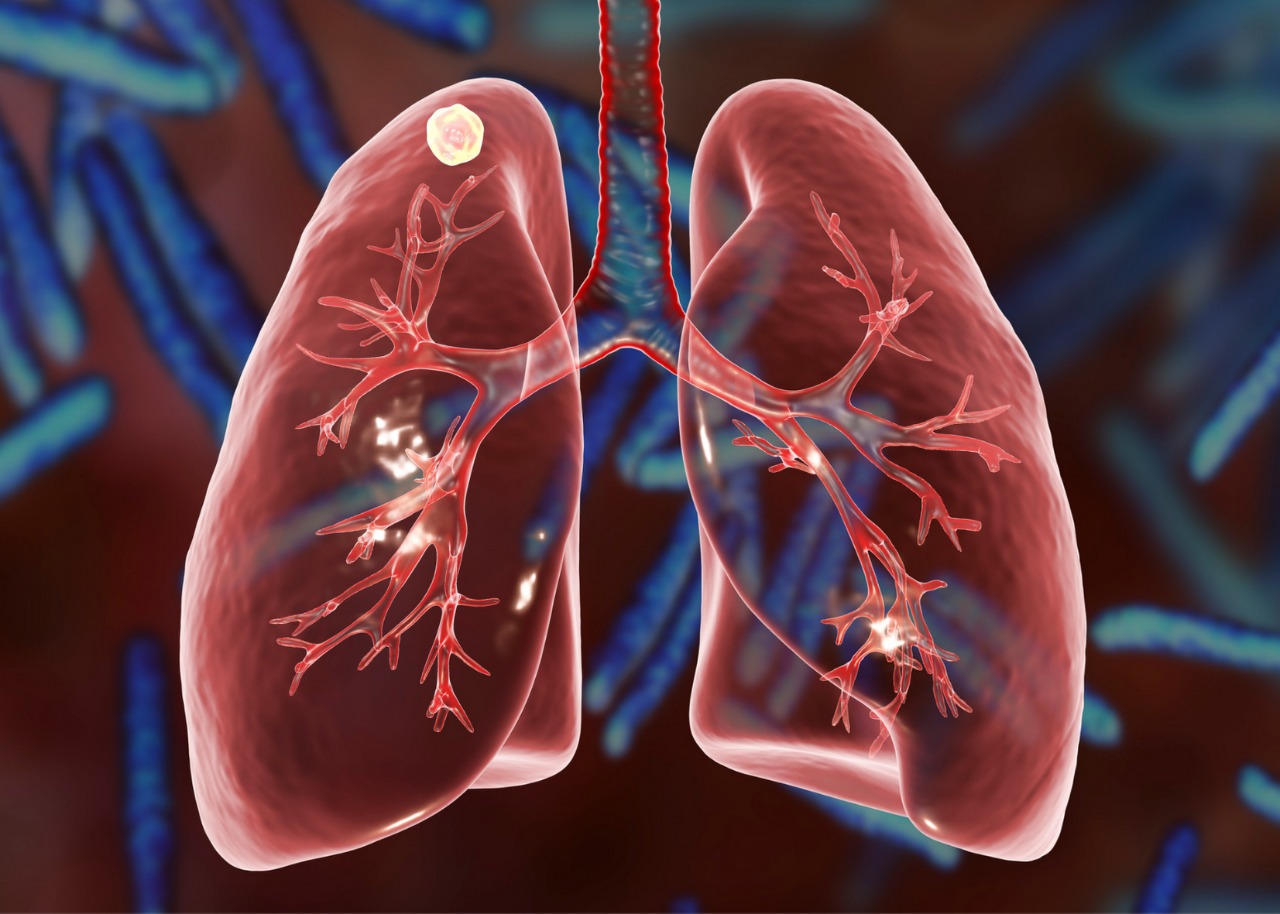

Ciência e Saúde

Tuberculose mata (quase) tanto quanto a covid-19

De acordo com um levantamento da Organização Mundial da Saúde (OMS), existem hoje duas bilhões de pessoas infectadas pelo Mycobacterium tuberculosis sem saber, o que corresponde a um terço da população mundial. A maioria dessas pessoas sequer sabem que estão infectadas, mas seguem transmitindo a enfermidade. Dentre elas, 9 milhões desenvolverão sintomas da doença e, deste, 2 milhões morrerão a cada ano. Ou seja, quase tanto quanto o covid-19, que em um ano matou 2,5 milhões de pessoas.